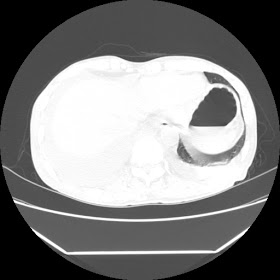

A 56 years old man with

HRCT done on summer season starting 2016